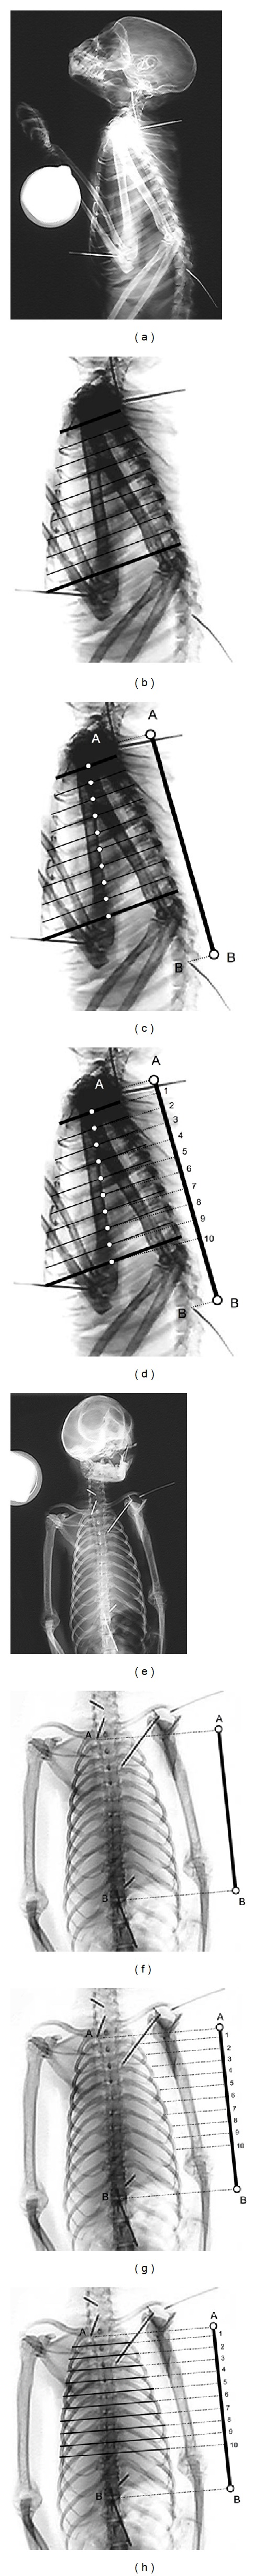

In hominoids, the broad thorax has been assumed to contribute to their dorsal scapular position. However, the dorsoventral diameter of their cranial thorax was found in one study to be longer in hominoids. There are insufficient data on thoracic shape to explain the relationship between broad thorax and dorsal scapular position. The current study presents data on multilevel cross-sectional shape and volume distribution in a range of primates. Biplanar radiographs of intact fluid-preserved cadavers were taken to measure the cross-sectional shape of ten equally spaced levels through the sternum (called decisternal levels) and the relative volume of the nine intervening thoracic segments. It was found that the cranial thorax of hominoids is larger and broader (except in the first two decisternal levels) than that of other primates. The cranial thorax of hominoids has a longer dorsoventral diameter because the increase in dorsoventral diameter caused by the increase in the volume of the cranial thorax overcompensates for the decrease caused by the broadening of the cranial thorax. The larger and broader cranial thorax in hominoids can be explained as a locomotor adaptation for scapular gliding and as a respiratory adaptation for reducing the effects of orthograde posture on ventilation-perfusion inequality.